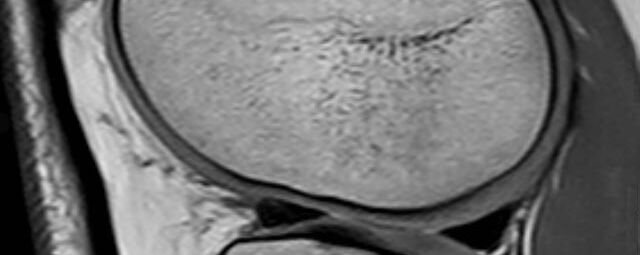

Gelenke

• Beurteilung von Knochen, Bändern und anderen Weichteilstrukturen der Gelenke nach Unfall.

• Arthrosediagnostik (Knorpelschaden)

• Impingement-Symptomatik

• Ursachenklärung bei wiederholter spontaner Gelenkluxation

• Ausbreitungsdiagnostik bei Gelenkentzündung, z.B. im Rahmen von rheumatischen Grunderkrankungen